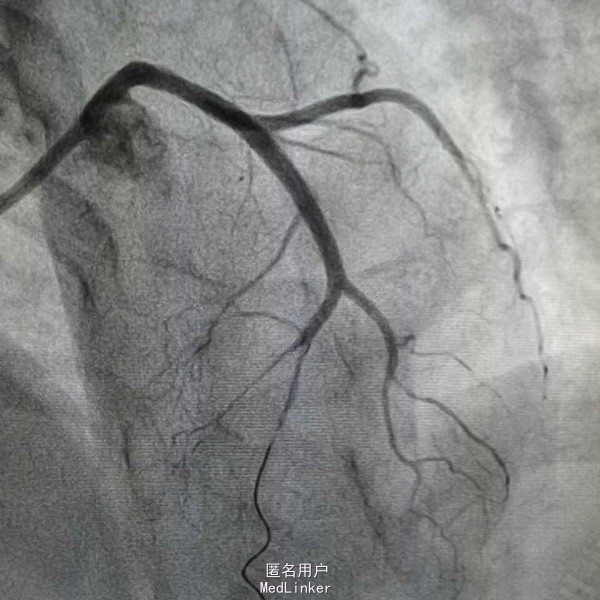

造影示左主干闭塞,如图,预扩后快速送入支架行冠脉再通,此病人心电图很难判断左主干病变,值得警惕